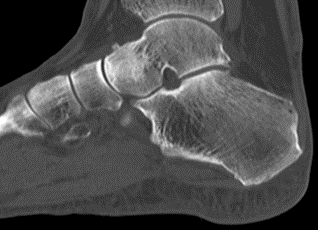

Eine CT Untersuchung 11 Wochen nach dem Unfall bestätigte diesen Befund. (Abb.4)

Abb.4 CT 11 Wochen nach dem Unfall